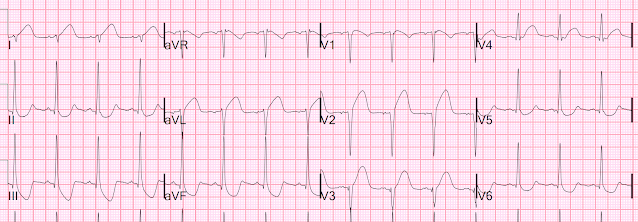

Because of this CT interpretation, they recorded an ECG:

It is clear that this transmural ischemia (STEMI/OMI) could have been diagnosed earlier with an ECG.

The ECG is all but diagnostic of LAD occlusion (Occlusion MI, or OMI)

Interesting case for this unfortunate young man who died from his severe head injury. The initial ECG in today's case (which I have reproduced in Figure-1) is markedly abnormal — with profound, coved ST elevation in not only the anterior leads — but also high lateral leads I and aVL + mirror-image opposite inferior lead ST depression (to the aVL ST elevation) + marked right axis (consistent with LPHB) + and not only loss of anterior R waves, but a fragmented downslope to the S wave in lead V3 (often itself a sign that there has been anterior infarction).

Dr. Smith lists 2 potential reasons to explain these ECG findings: i) Acute LAD occlusion; and, ii) Based on Echo findings — Takotsubo cardiomyopathy.

I would add a 3rd potential contributing factor = severe CNS injury — which is notorious for causing QTc prolongation with often unpredictable ST-T wave abnormalities that often result in “pseudo-infarct” patterns.

Obviously — severe CNS injury is not the only cause of ECG abnormalities in today’s case given marked Spectral CT and Echo abnormalities — but I thought the shape of elevated and depressed ST-T waves on today’s initial ECG to be distinctly unusual in the degree of T wave “fattening” (rounding out) at T wave peak and/or nadir (in those leads where the ST is depressed). I thought at least a portion of the unusual ECG findings in Figure-1 may be attributable to severe CNS injury.

| Figure-1: The initial ECG in today's case — obtained from a young man with severe blunt trauma with severe head injury (See text). |